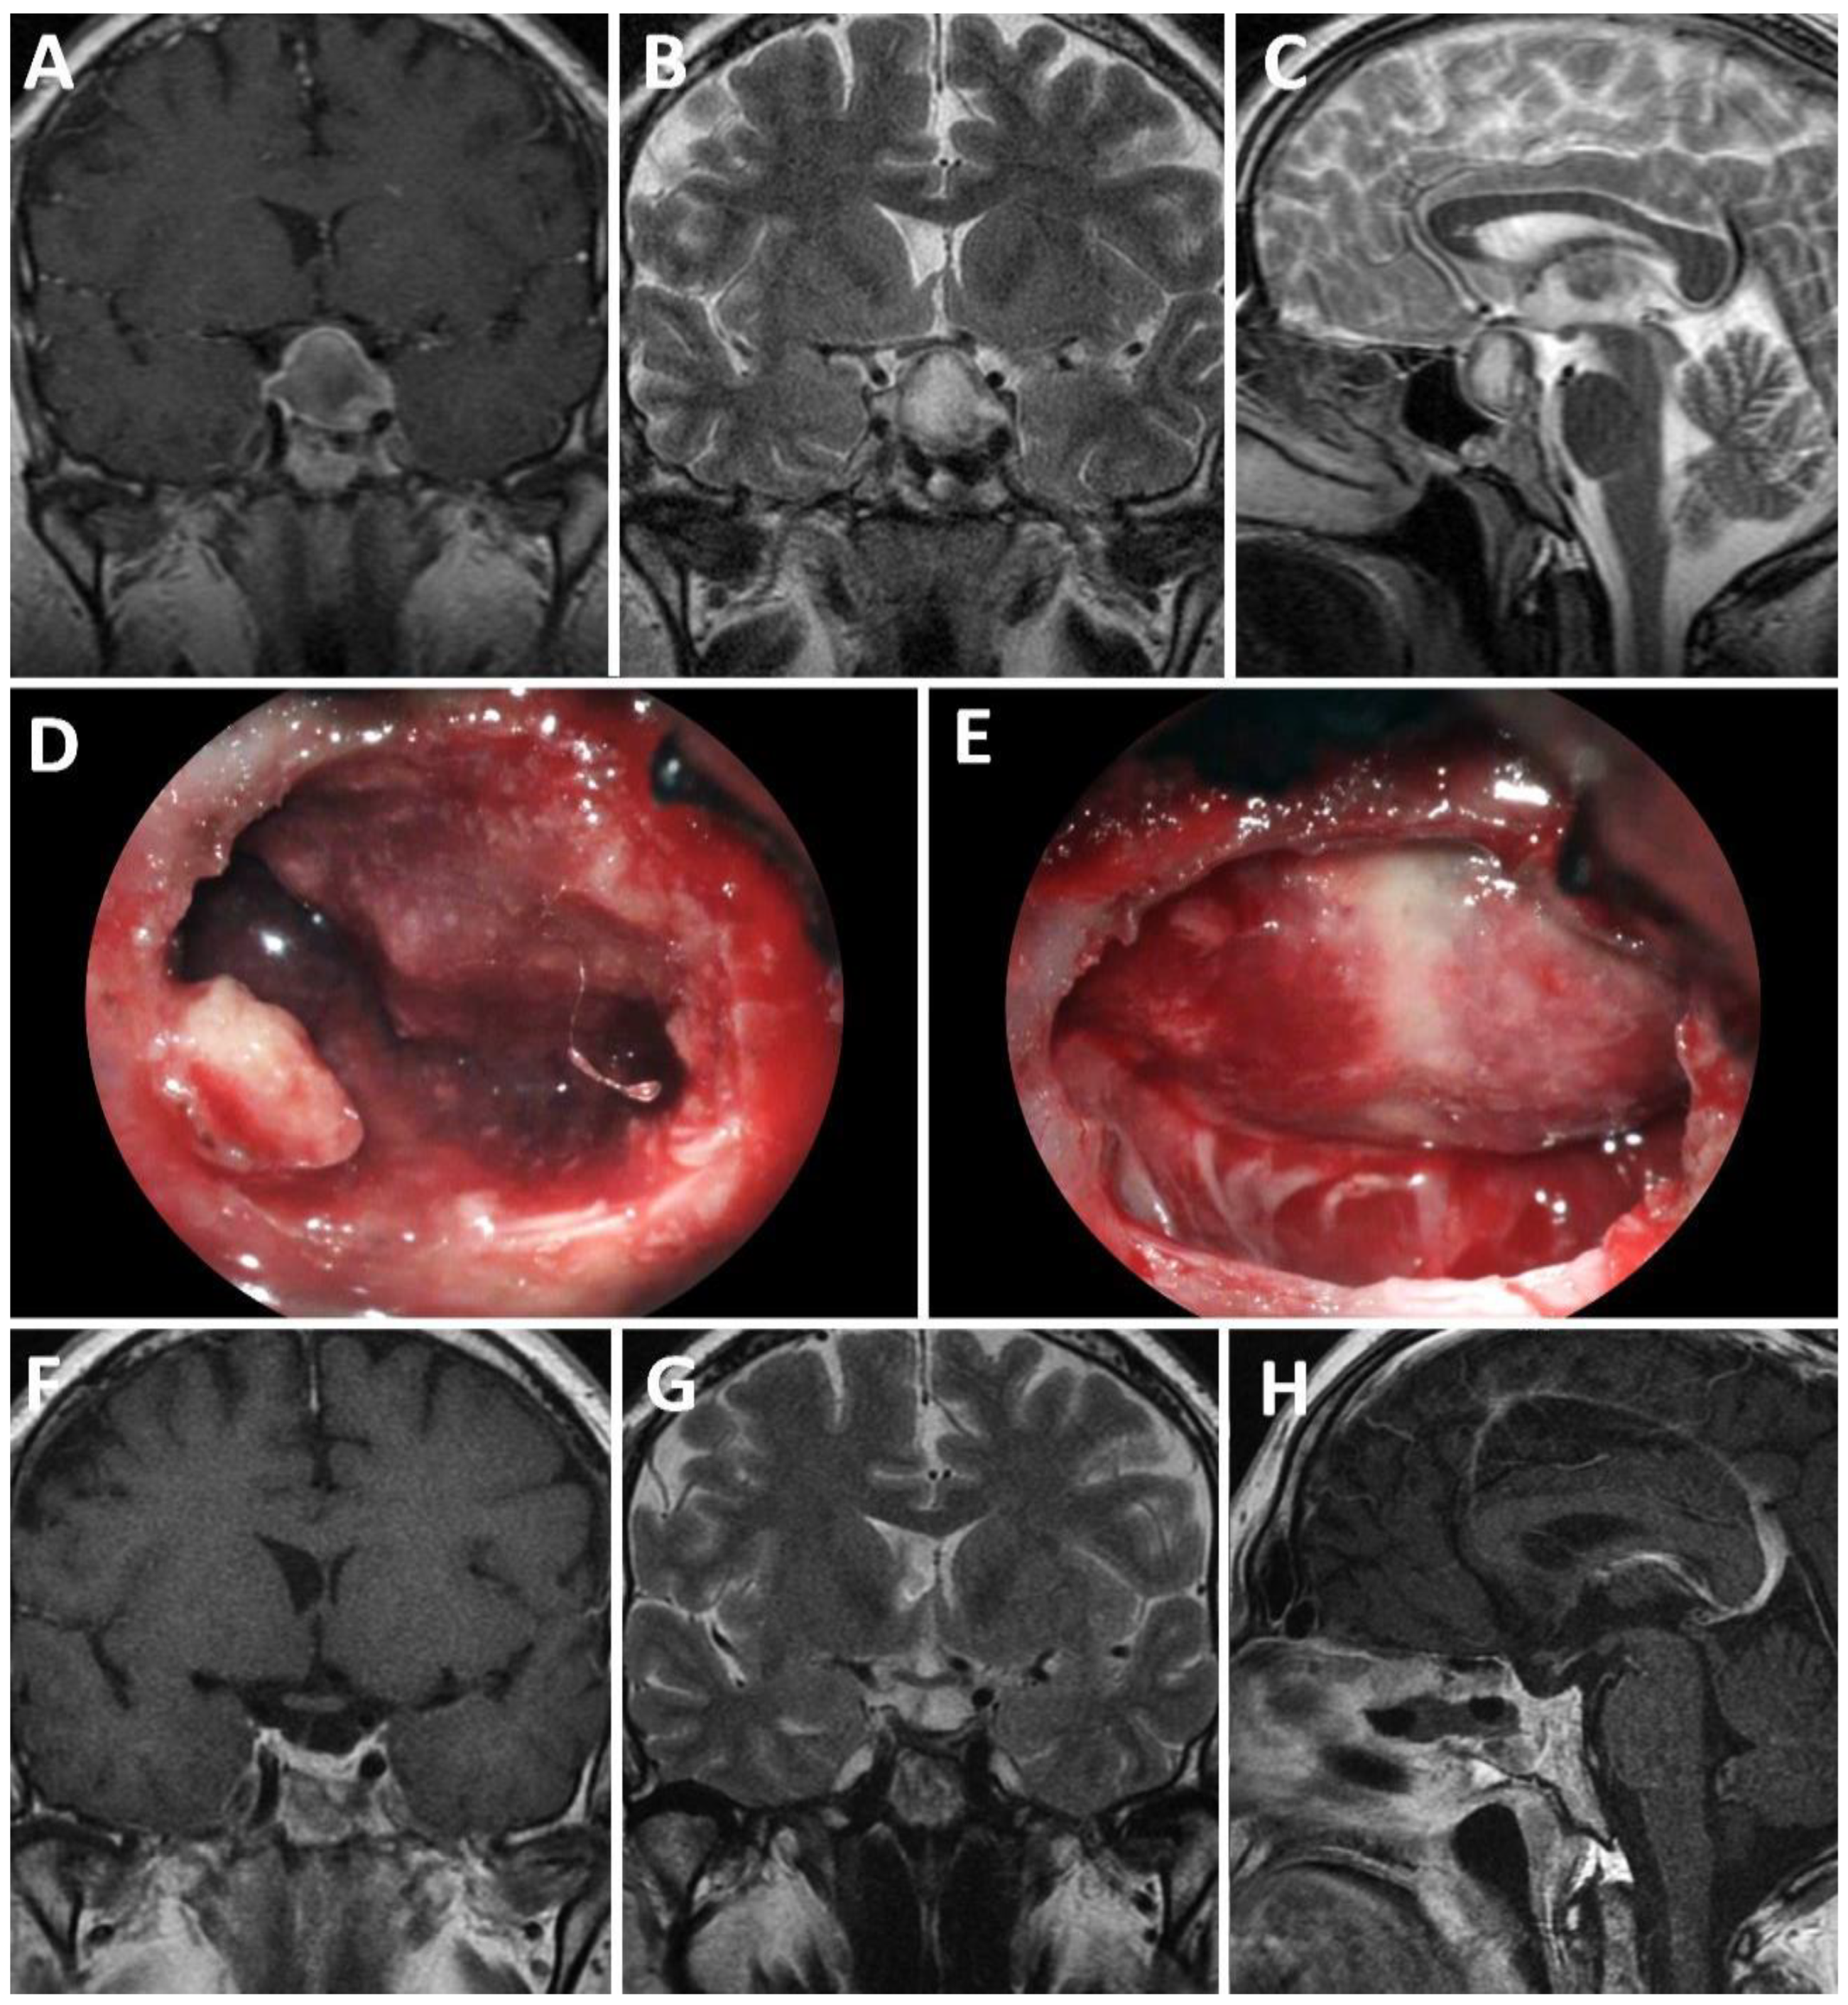

4.2.5. Differentiation Sellar Barrier Subtypes on MRI and during Surgery

- -

- Strong: barrier thickness more than 1 mm.

- Weak: barrier thickness less than 1 mm.

- Mixed: T1-weighted volumetric sequences displaying both types of thicknesses in different areas of the sellar barrier.

- Strong: gland and/or dura mater are observed on the roof of the pituitary fossa.

- Weak: roof composed only of arachnoid.

- Mixed: a portion of the roof is covered by gland or dura mater and another portion by arachnoid.

4.2.6. Correlation between MRI, Intraoperative Findings, and Risk of CSF Leakage